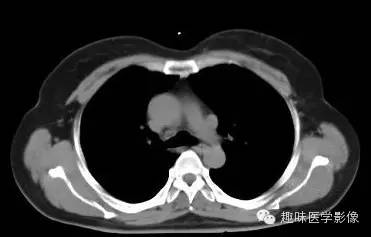

女,53岁,胸憋气短。

两肺未见明显异常。纵隔左侧见血管影,经主动脉弓与左肺肺门之前向下走行,汇入冠状静脉窦。

永存左上腔静脉